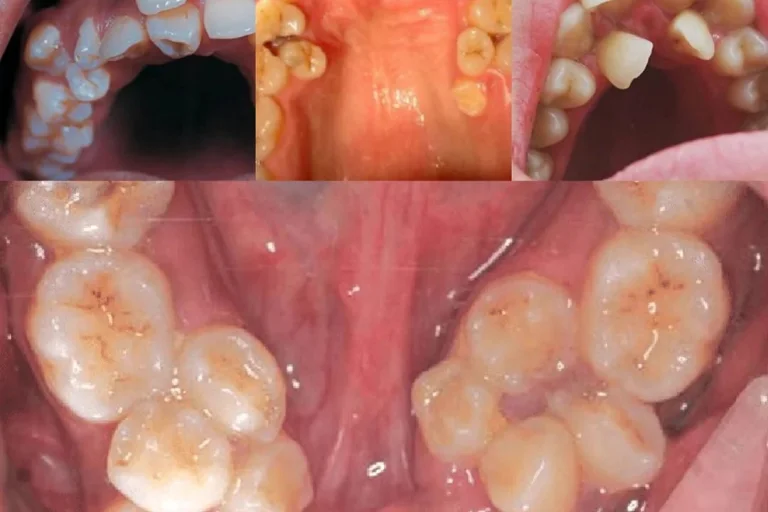

When you are a child, you may grow 20 primary teeth, which will be replaced by 32 permanent teeth. But in very rare cases, you may develop extra teeth that can either be permanent teeth or primary teeth. These extra teeth are also called supernumerary teeth.

Children with more than 20 teeth and adults with more than 32 teeth have hypodontia. These extra teeth can emerge in any part of the mouth but are most commonly found near the upper front teeth (mesiodens) or near the molars (paramours and distomolars).

- Mesiodens: Extra teeth that develop between the two central upper front teeth.

- Paramolars: Additional teeth that grow near the molars.

- Distomolars: Teeth that emerge behind the third molars (wisdom teeth).

Extreme Hyperdontia

Extreme hyperdontia refers to cases where multiple extra teeth develop. It is a rare condition and is often associated with genetic disorders such as Cleidocranial Dysplasia or Gardner’s Syndrome. Extreme hyperdontia may require extensive dental treatments, including multiple extractions and orthodontic correction.